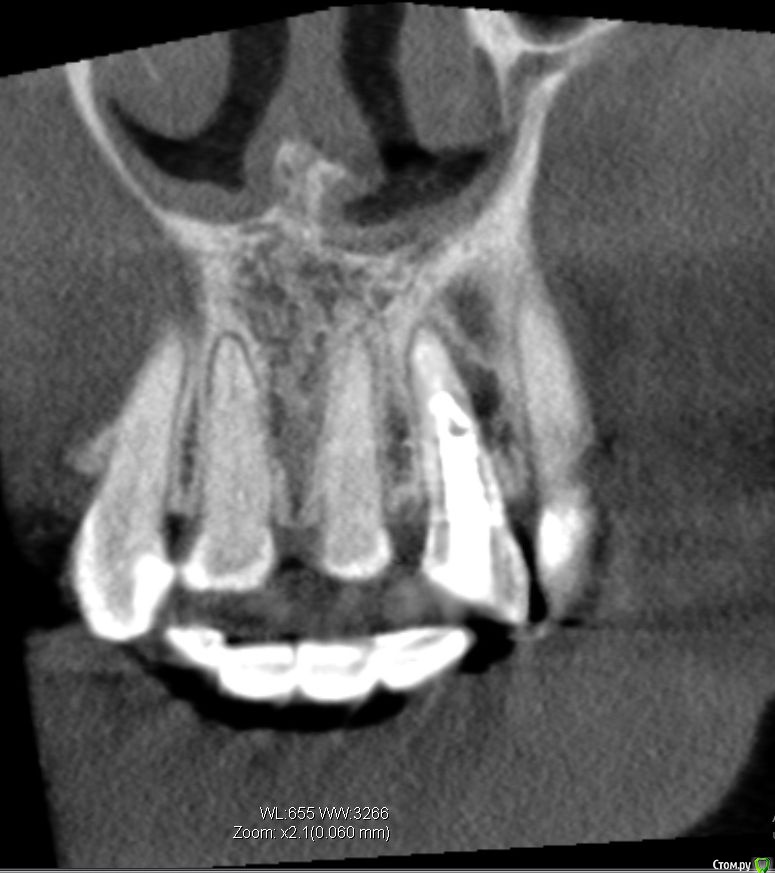

Lanasvlisa Опубликовано 21 апреля, 2017 Поделиться Опубликовано 21 апреля, 2017 Добрый вечер, уважаемые врачи! Вопрос по зубу 22, он леченый-перелеченный, сейчас на корне обнаружена киста, на десне над зубом свищевой ход. Какое ваше мнение: 1) удалять зуб и вместе с ним уйдет воспаление, прочищать все и заниматься имплантацией; или 2) можно каким-то образом удалить кисту, отсечь корень (читала о таком), но сам зуб не удалять? Если всё-таки 1), то можно ли осуществить в данном случае одномоментную имплантацию с нагрузкой? или можно одномоментную, но без нагрузки...? Спасибо огромное всем, кто посмотрит снимки и выразит свое экспертное мнение! С уважением, PS: прикрепляю скриншот из программы, но если этого недостаточно для определения диагноза и плана вмешательства, то скину ссылку на весь архив. Ссылка на комментарий

колесников Опубликовано 21 апреля, 2017 Поделиться Опубликовано 21 апреля, 2017 Резецировать там нечего,во время эндодонтического лечения произошла перфорация стенки корня зуба,вокруг этого участка очаг деструкции костной ткани. Это не лечится.По выставленной вами картинке объём деструкции не понятен. Решить возможность одномоментной имплантации и тем более немедленной нагрузки может только ваш лечащий доктор ,по результатам кт и в соответствии со своим опытом. Ссылка на комментарий

колесников Опубликовано 24 апреля, 2017 Поделиться Опубликовано 24 апреля, 2017 Полностью поддерживаю. Имплантировать лучше одномоментно и с пластикой десны. Делать отсрочено ,с консервацией лунки,тоже возможно,но мне лично не очень нравится. Если в первом варианте имплант контактирует с вашей костью,то во втором -с искусственной,что иногда приводит к неудачам. Также частенько происходит усадка десны у соседних зубов,исчезает сосочек. Съёмный протез-бабочка только усугубляет эту усадку. Ссылка на комментарий